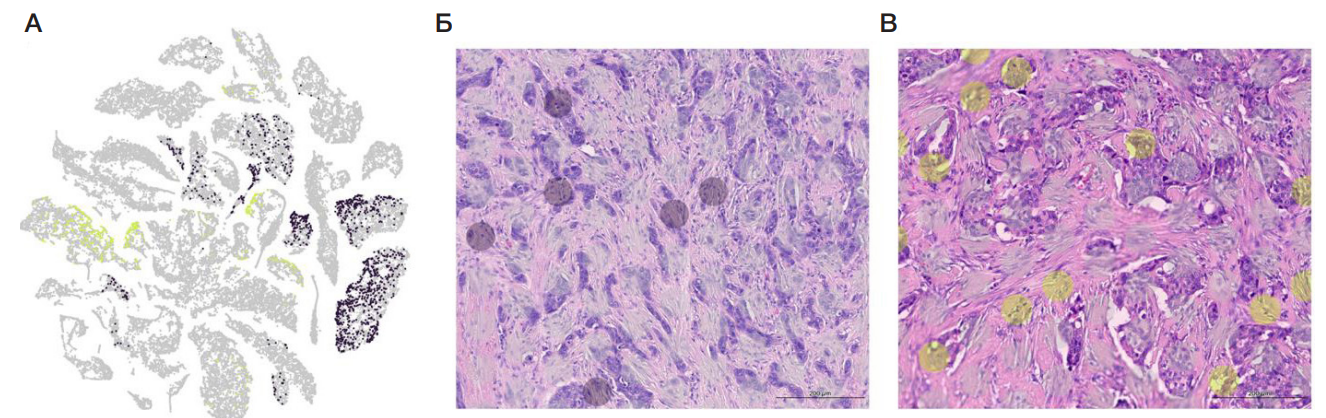

Особенности транскриптомного профиля FAP+-клеток в опухолях молочной железы различных молекулярно-биологических подтипов